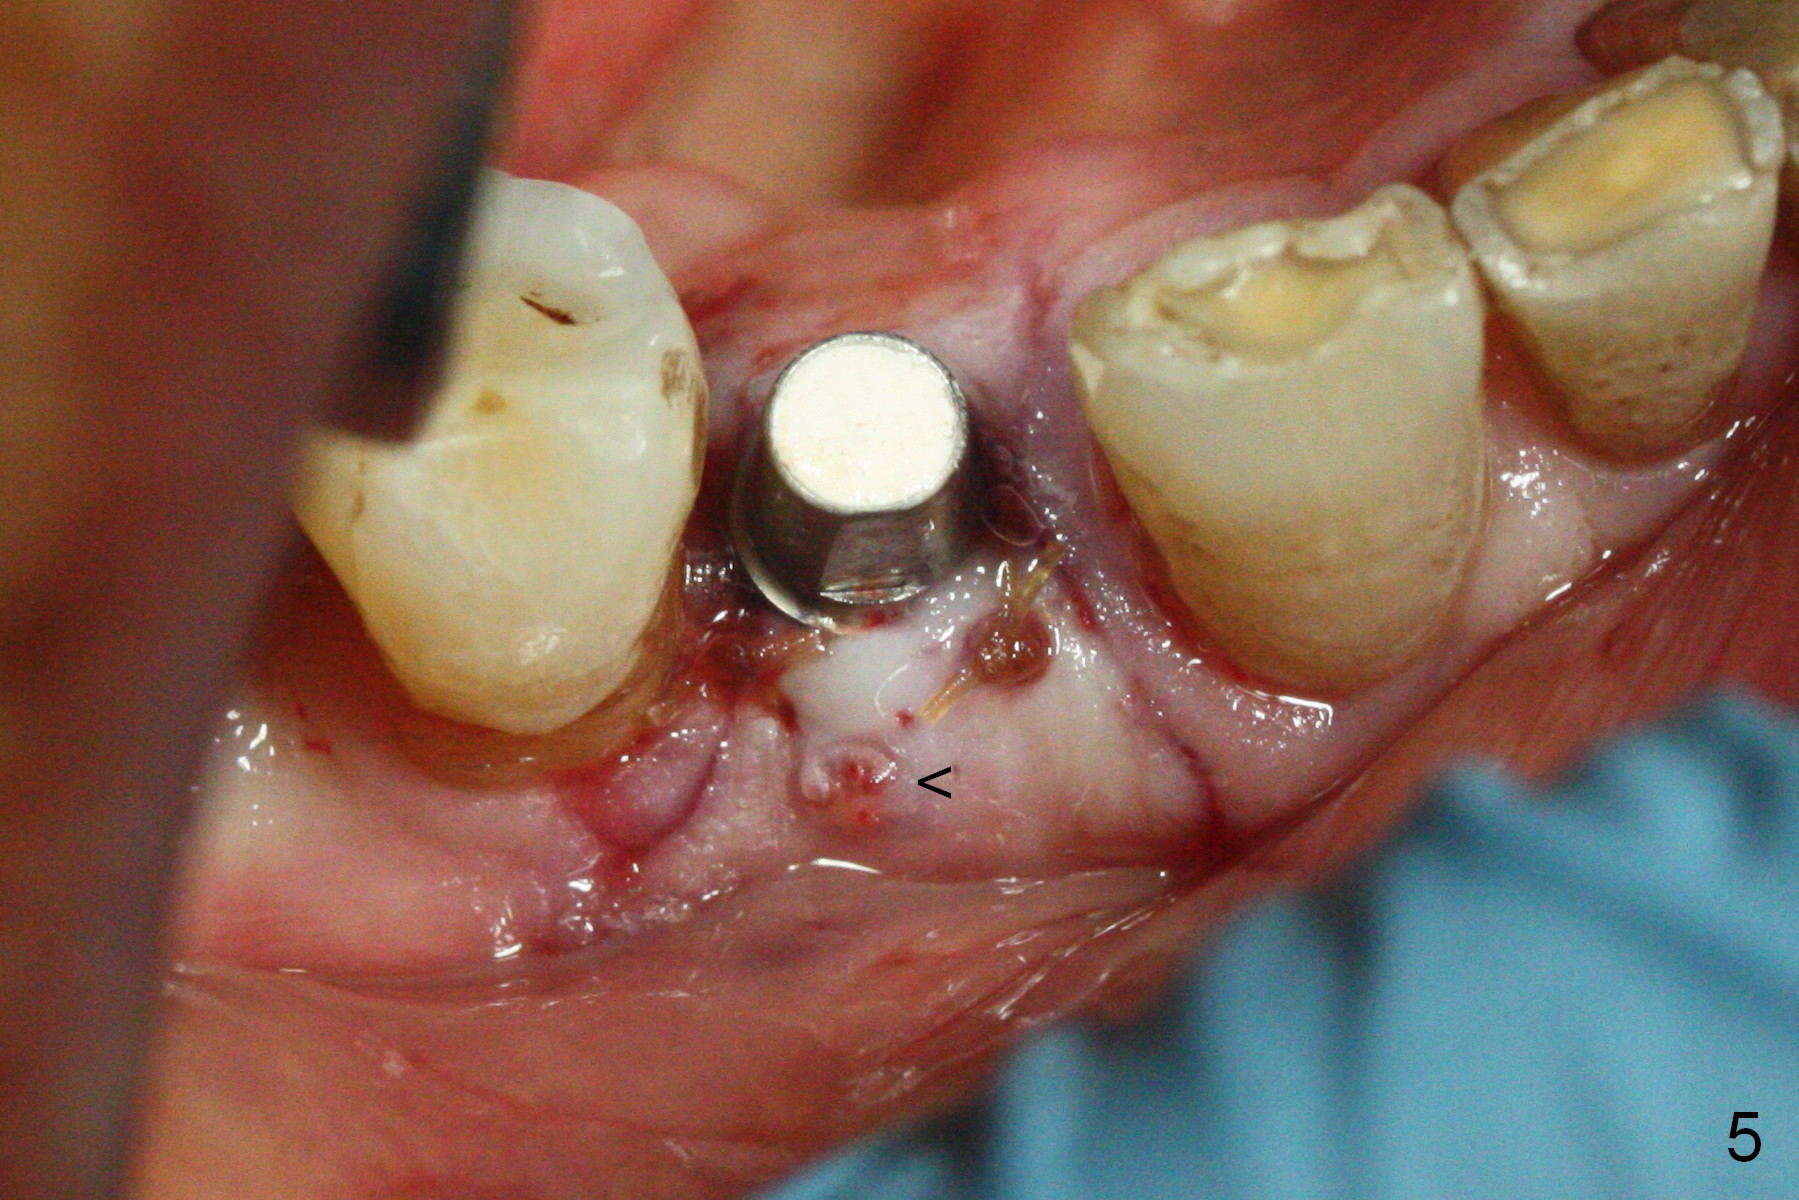

In fact the mesiodistal space of the site of #28 is within normal limit. The buccal plate atrophy is striking (Fig.1) with a fistula (^, associated with underlying residual root tip). When the flaps are raised, the ridge is triangular with the lingual plate (Fig.2 *) higher than the buccal one. Because of the slope, the multiple-drill approach is adopted in stead of single-drill one, because the marking bur is wobbling after 1.6 mm osteotomy at 13 mm (Fig.3). After placement of a 4x11 mm implant, a 4.5x4(2) mm abutment is inserted (Fig.4). The abutment and the implant act as a mesh (framework) so that bone graft and collagen membrane can be laid upon them buccolingually. When the flaps are sutured, there is less tension than that without the abutment. Furthermore, the buccal tissue volume seems to be increased (Fig.5 (<: fistula, which should heal soon), as compared to Fig.1). Tale photos to show effectiveness of the simultaneous GBR and disappearance of the fistula. Three months postop (Fig.6,7 (incomplete abutment seating)), the implant is loaded for intrusion of the opposing supraerupted tooth. The patient returns with chief complaint of food impaction between #27 and 28 three years 7 months post cementation; there is an open contact. Before pick up impression the distal convex surface of #27 is trimmed. The repaired crown has tight proximal contacts before (Fig.9,10) and after (Fig.11) retightening and cementation.